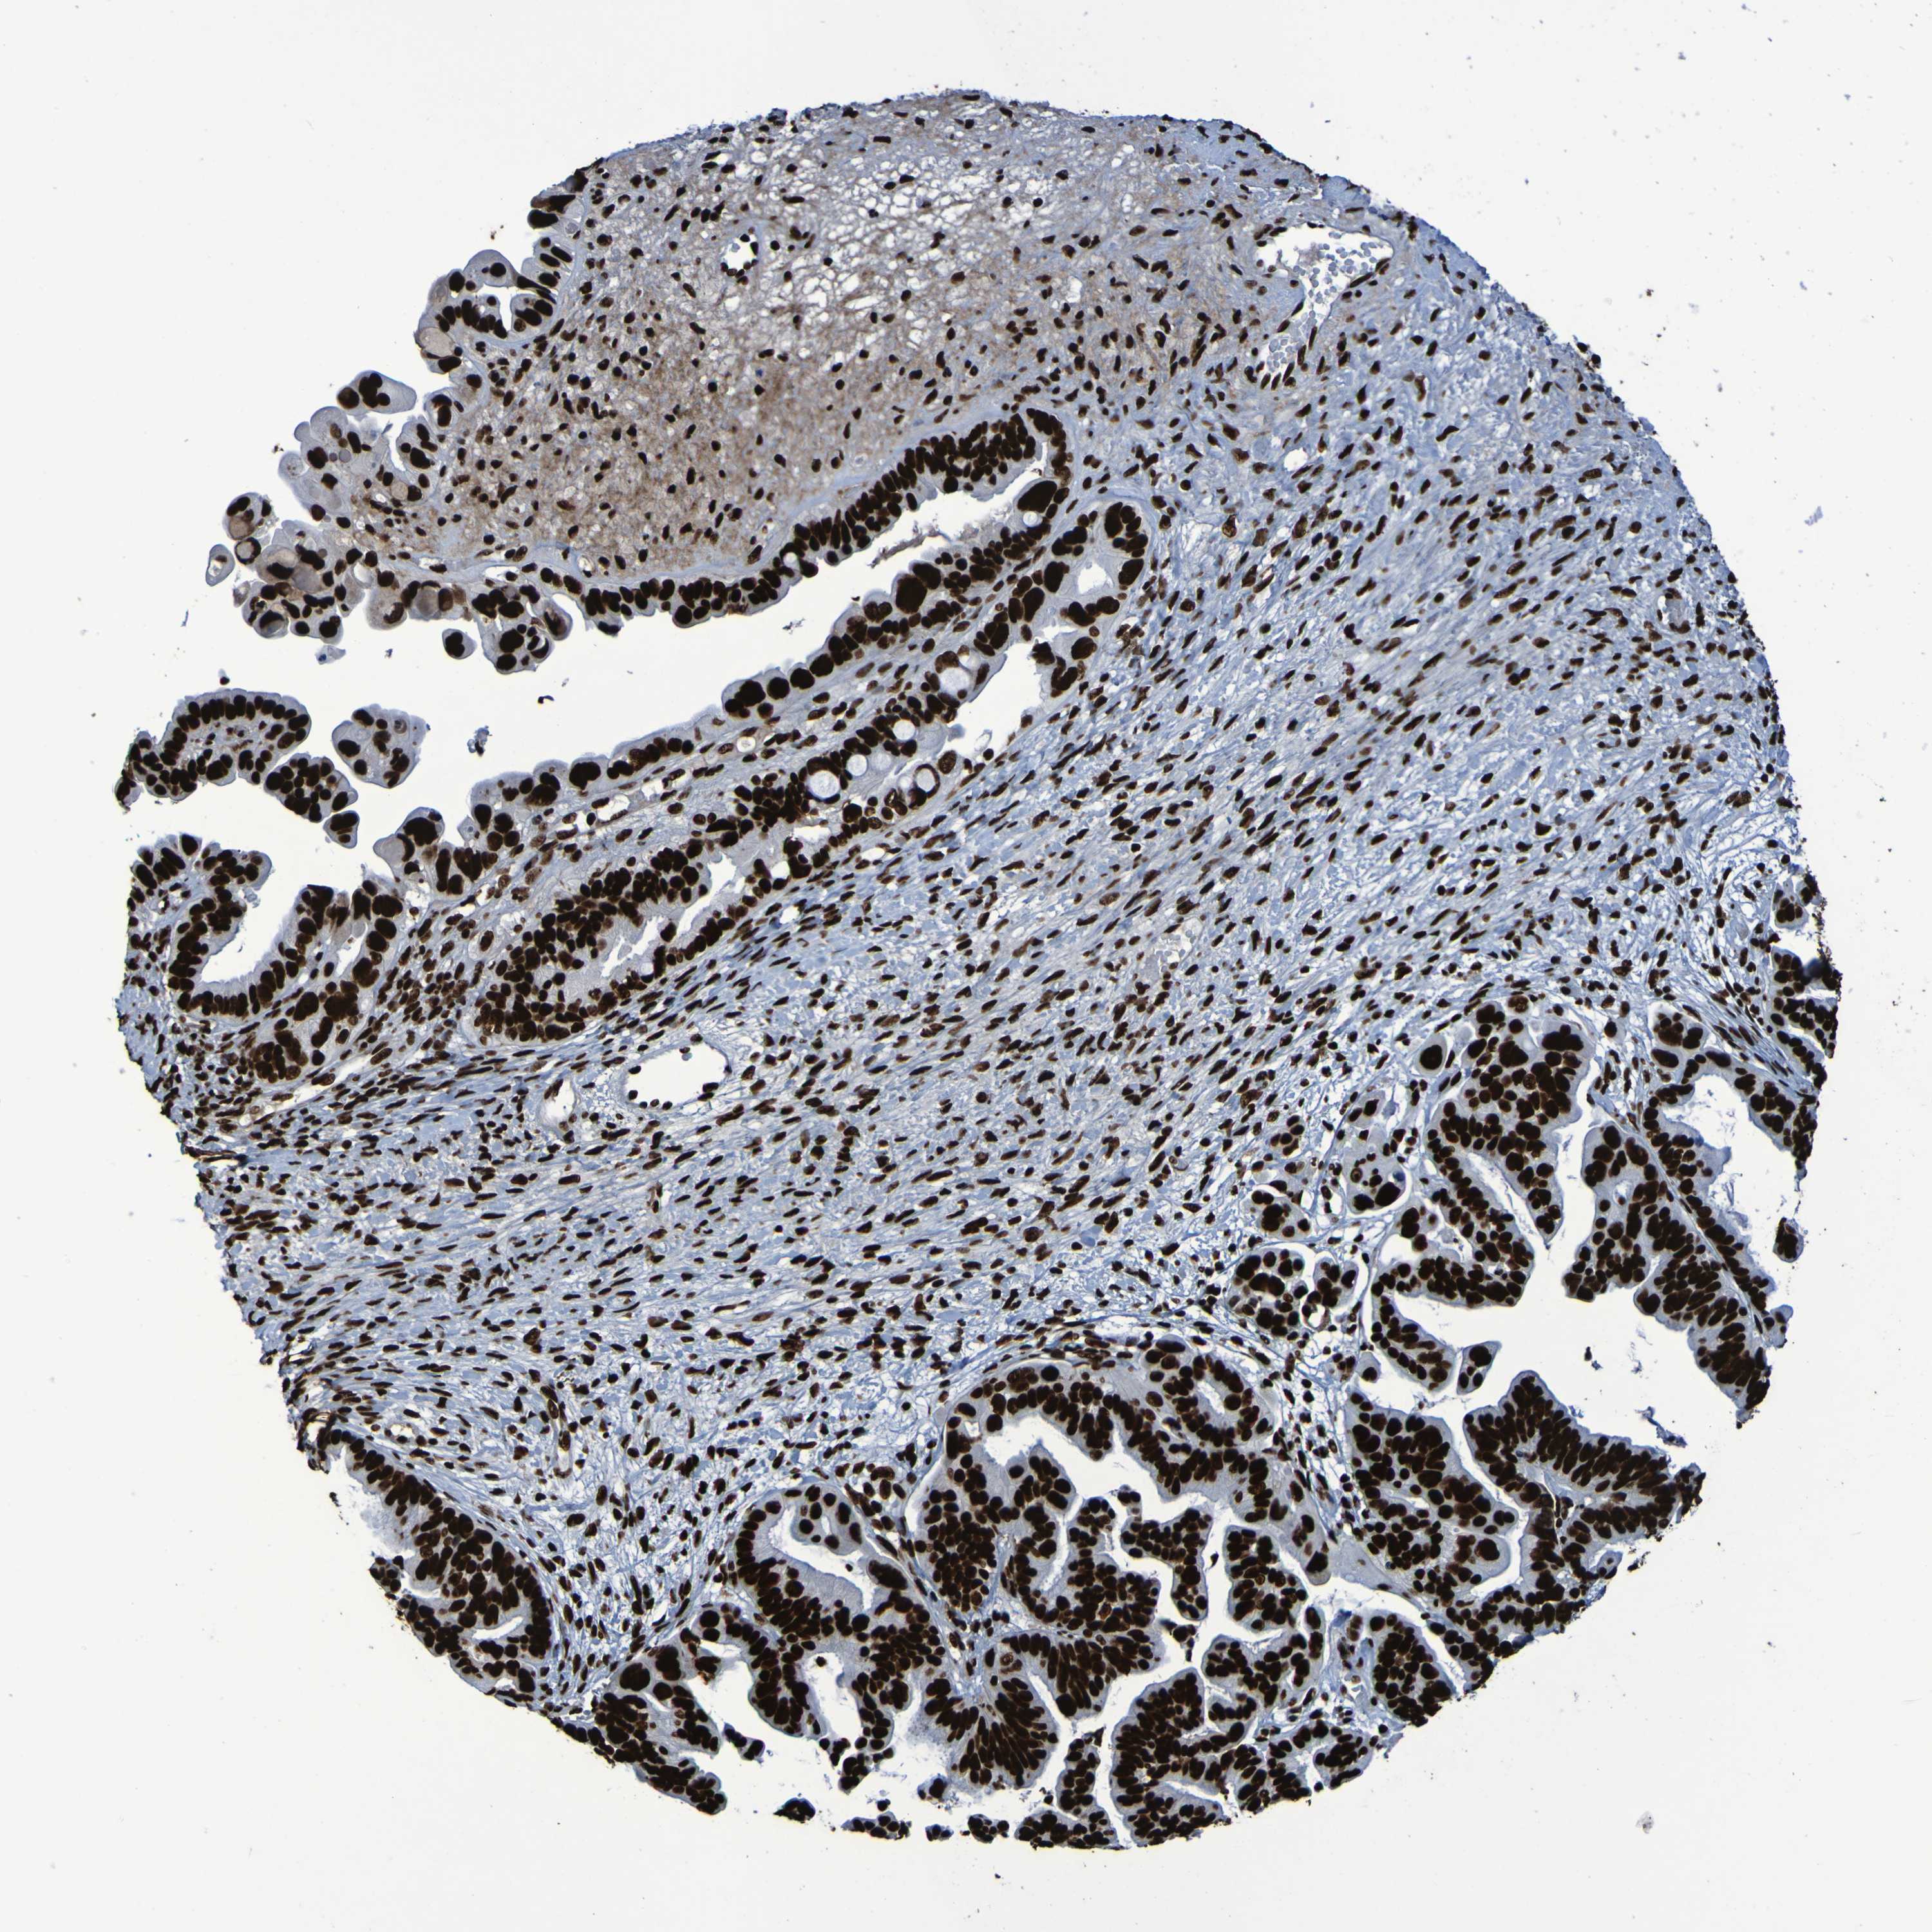

OVARIAN CANCER - Protein expressioni

A mouse-over function shows sample information and annotation data. Click on an image to view it in a full screen mode. Samples can be filtered based on level of antibody staining by selecting one or several of the following categories: high, medium, low and not detected. The assay and annotation is described here.

Note that samples used for immunohistochemistry by the Human Protein Atlas do not correspond to samples in the TCGA dataset.

Antibody stainingi

Antibody staining in the annotated cell types in the current human tissue is reported as not detected, low, medium, or high, based on conventional immunohistochemistry profiling in selected tissues. This score is based on the combination of the staining intensity and fraction of stained cells.

Each image is clickable and will lead to virtual microscopy that enables deeper exploration of all samples and also displays staining intensity scores, fraction scores and subcellular localization as well as patient and tissue information for each sample.

Antibody HPA011384

Antibody CAB012983

Cystadenocarcinoma, serous, NOS

Carcinoma, endometroid

Cystadenocarcinoma, mucinous, NOS

Carcinoma, NOS